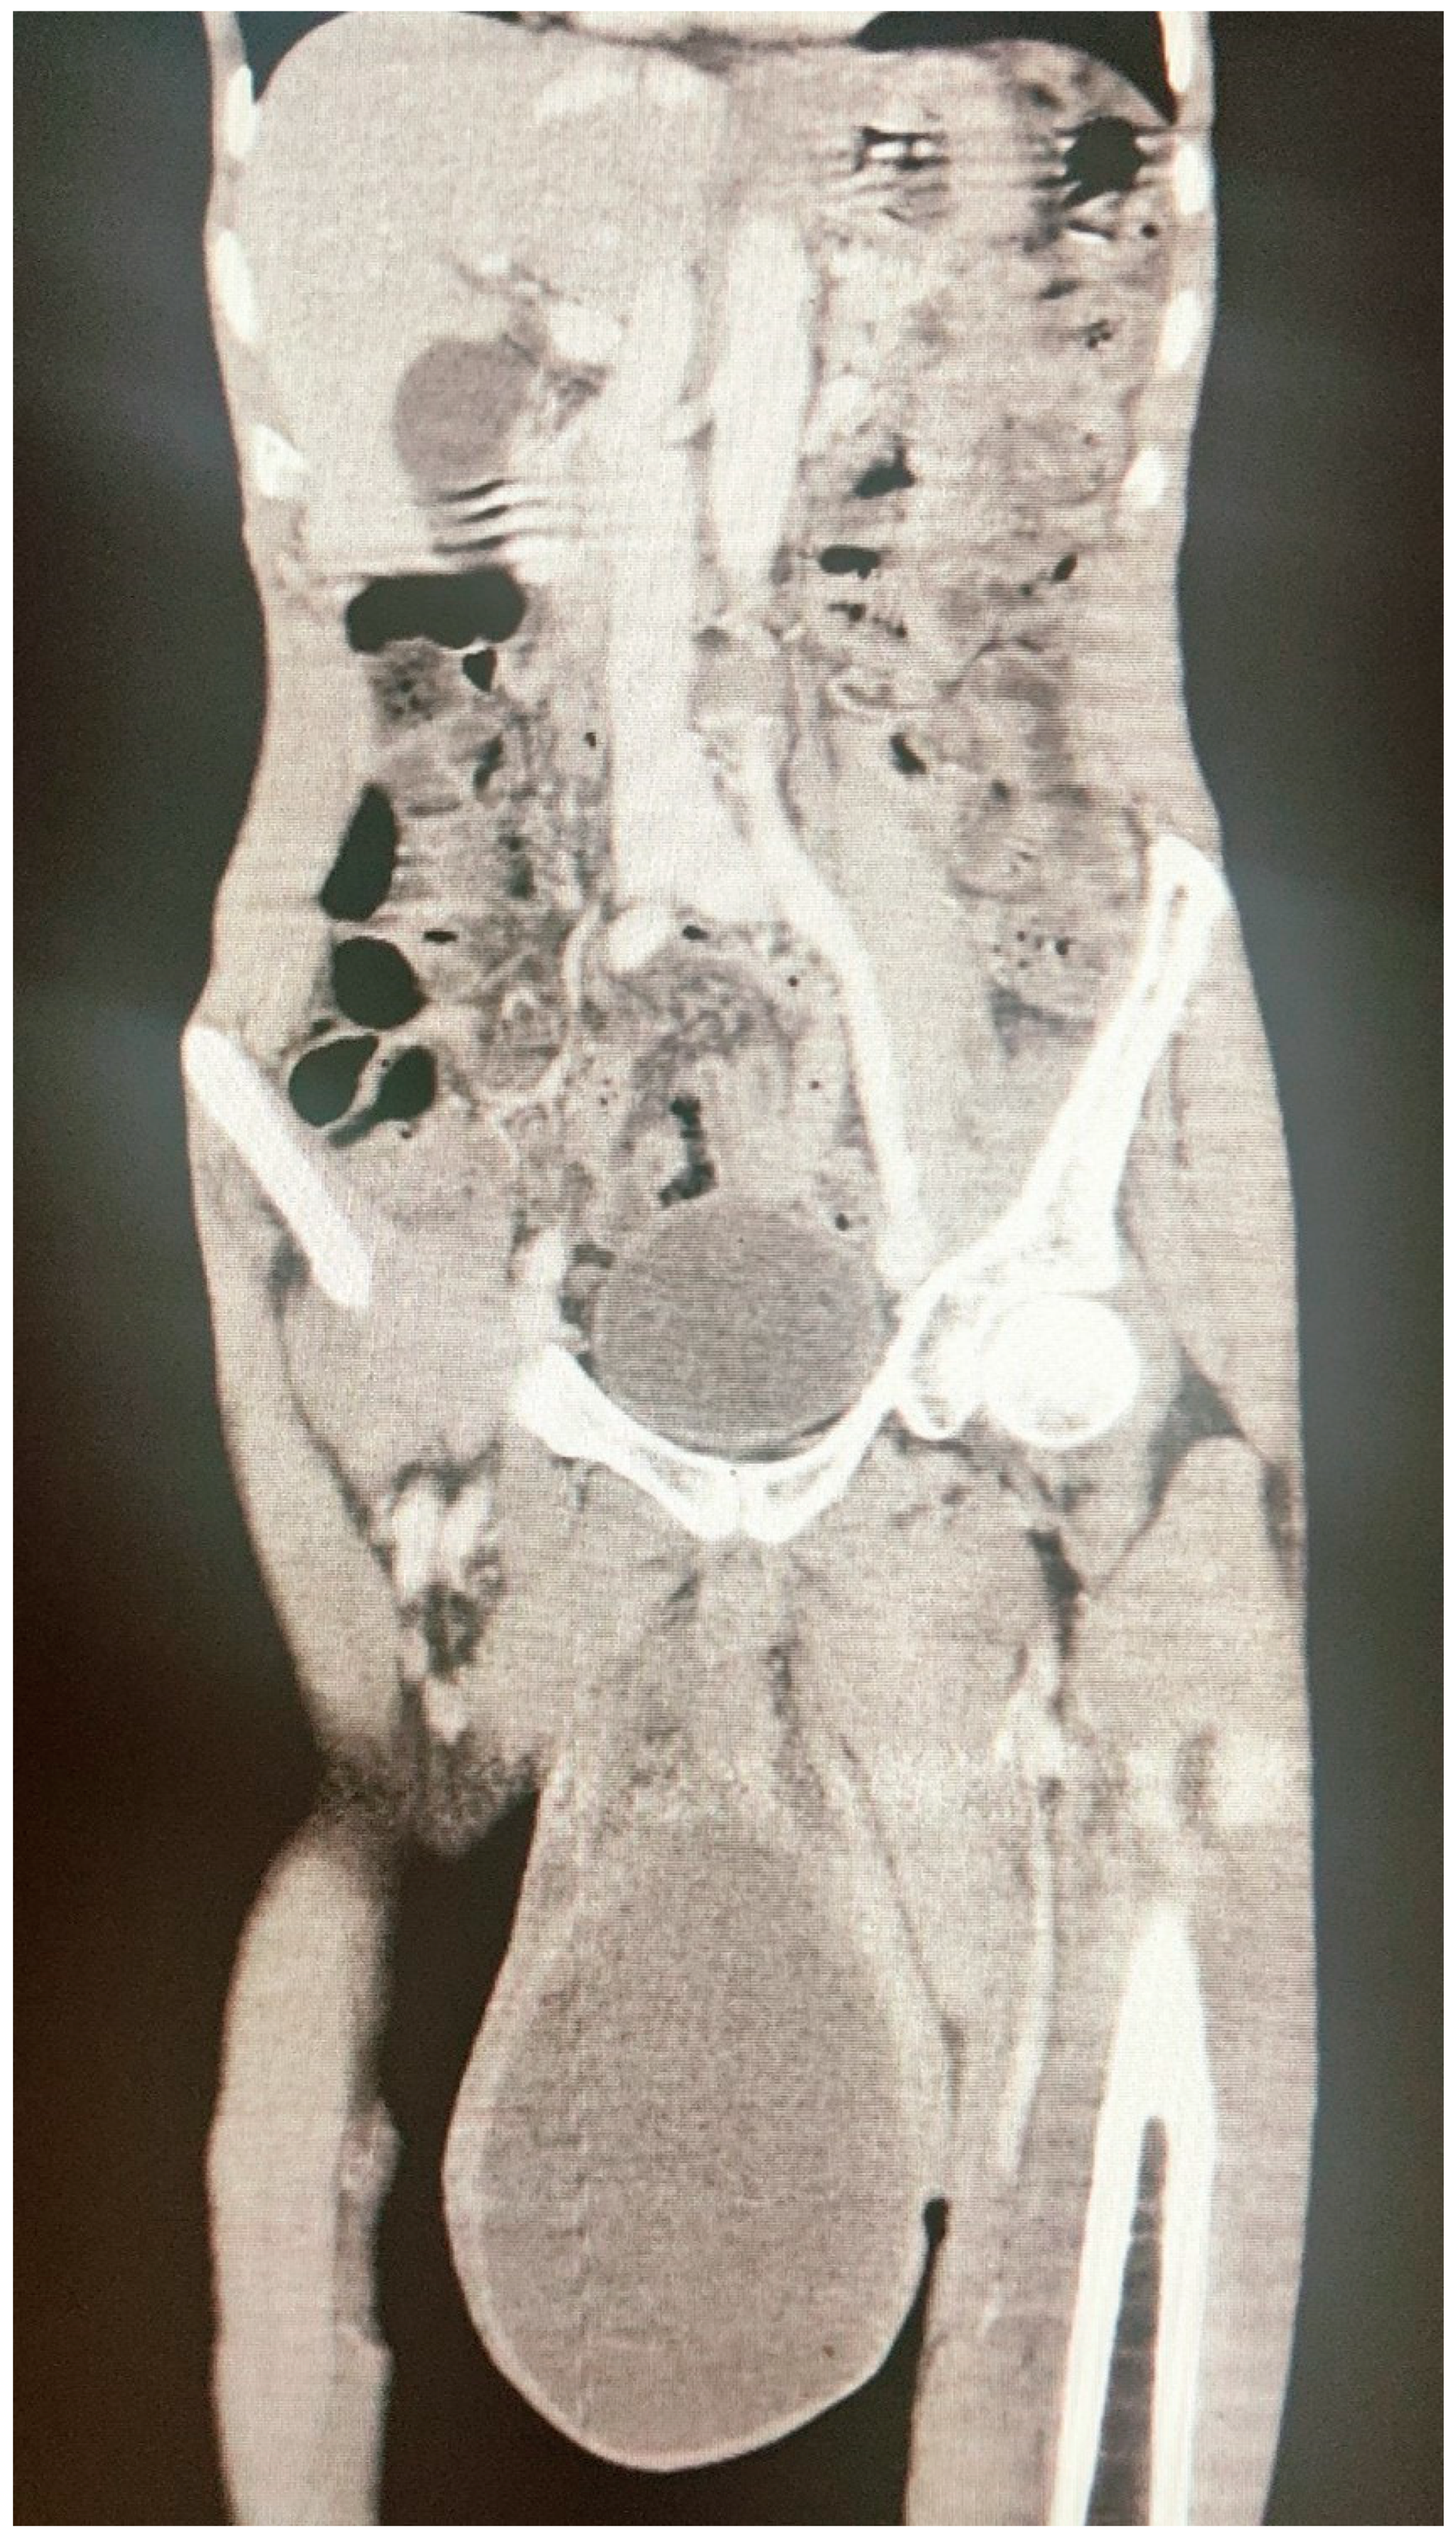

Isolated Hydatid Cyst: A Misleading Diagnosis

About Our Case